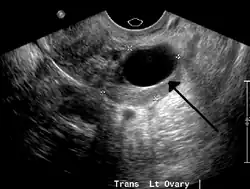

A simple ovarian cyst of most likely follicular origin | |

Transvaginal ultrasonography of a hemorrhagic ovarian cyst, probably originating from a corpus luteum cyst. The coagulating blood gives the content a cobweb-like appearance.